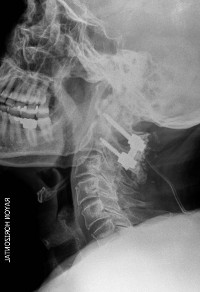

Hernie Discale Cervicale - Névralgie Cervico-Brachiale

Myélopathie Cervicale